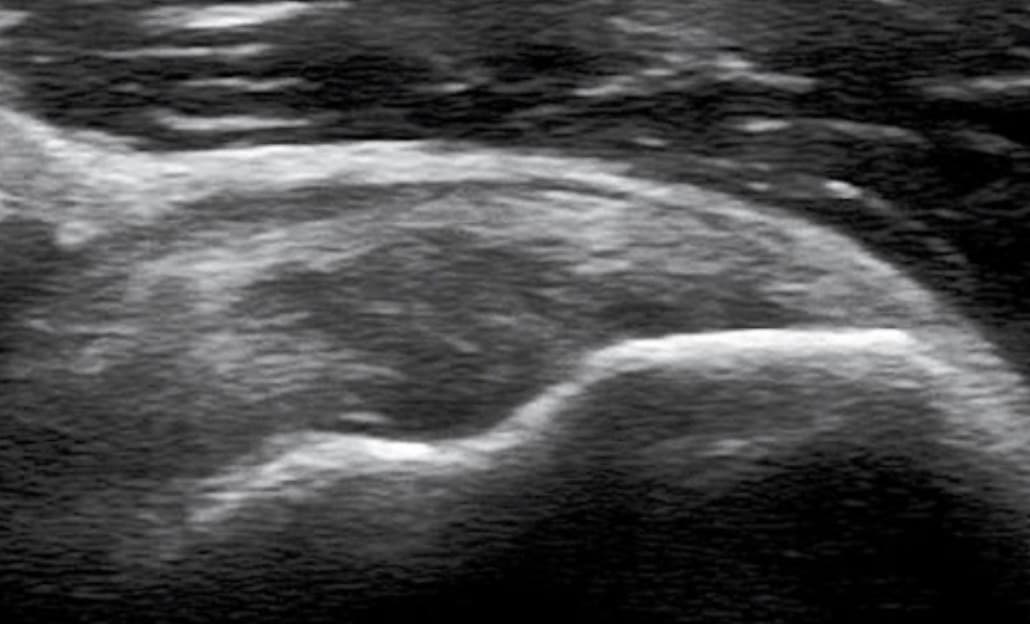

근육과 힘줄의 손상은 급성과 만성으로 나뉜다. 급성손상은 외부로부터의 직접 충격, 근육 수축 중에 발생하는 뻗침 손상, 관통상 등이 있다. 급성 근육손상은 임상적으로 세 가지 등급으로 나뉜다. 등급 1은 근육섬유의 손상이 없는 것이고, 등급 2는 근육의 부분 손상과 근육의 힘이 감소하는 것이며, 등급 3은 근육의 전체층 째짐이다. 근육손상의 초기에는 좌상과 출혈 때문에 낮은 에코로 보인다. 근육 전체층 찢어짐은 특징적으로 근육의 연속성이 없어지고, 끊어진 근육의 아래 끝과 이끝 사이가 벌어지게 되며, 수동적 근육운동 또는 능동적 수축에서 더욱 또렷해진다. 혈종은 시간이 지남에 따라 점점 낮은 에코로 변한다. 연조직의 출혈이 흡수되면 혈종의 크기가 작아지고, 혈종주위의 에코는 증가한다. 에코 없는 부위는 장액주머니로 남는다.

급성 근육손상의 초음파 이미지 외부로부터 받은 직접 충격에 의한 근육손상은 혈종과 다양한 정도의 근섬유 째짐을 동반한다. 반면에, 근육수축 중에 발생하는 뻗침 손상은 특징적으로 근육-힘줄 경계부 손상이고, 흔히 두 개의 관절을 건너가는 긴 근육에서 잘 생긴다. 예를 들면 넙다리뒤근육, 장딴지근안쪽갈래 등이다. 근육의 구조를 이해하는 것이 중요하다. 장딴지근안쪽갈래처럼 근육이 반깃근 구조이면 근육의 가장자리에서 근-힘줄 경계부 손상이 잘 일어난다. 근육의 구조가 휘돌 이기근 또는 깃근육이면 손상이 먼쪽 근-힘줄경계부 또는 근육 내의 중심널힘줄에서 잘 생긴다.

출혈, 염증액, 손상 후 경과시간, 손상정도 등에 따라 근-힘줄 경계부 손상은 다양한 밝기의 높은 에코로 나타난다.